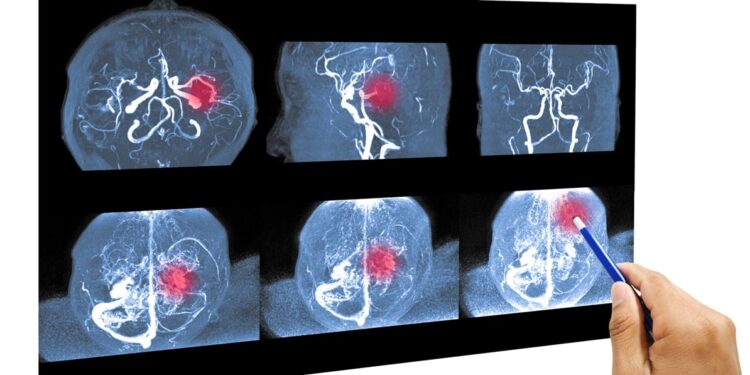

الصحة العامة: في تونس، جلطة دماغية كل ثلاثين دقيقة

تواجه تونس أزمة صامتة لكنها خطيرة: الجلطات الدماغية تضرب بوتيرة مقلقة، حيث يحدث حالة جديدة كل ثلاثين دقيقة ووفاة كل ساعتين. هذه الأرقام، التي كشفت عنها يوم الأربعاء البروفيسورة أمينة ڨرقوري، أخصائية الأعصاب، بمناسبة اليوم العالمي لمكافحة الجلطات الدماغية، تسلط الضوء على حالة طوارئ صحية غالبًا ما يتم التقليل من شأنها.